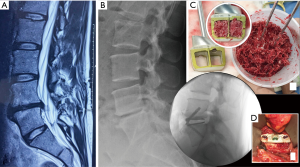

A 29-year-old male presented with low back pain on a background history of a microdiscectomy surgery performed at L5/S1. Despite non-surgical therapies over a 15-month period, ongoing low back pain resulted in loss of employment as a labourer. Magnetic resonance imaging (MRI) and bone scan were suggestive of degenerative change at the L5/S1 disc, with absence of changes elsewhere in the spine. An L5/S1 ALIF was performed (Figure 1). A Redmond (A-Spine ASIA, Taiwan) 3-screw integral fixation ALIF construct was performed in combination with allograft bone and DBF, with follow-up over a 12-month period. Fusion status at 12 months revealed a solid union, with minimal symptoms. He returned to his occupation as a labourer following confirmation of fusion on a computed tomography (CT) scan (Figure 1).

Both cases we report on had SCCO2 allograft bone and DBF mixed with approximately 2 mL of the patient’s blood (via a sterile sample provided by anaesthetic staff at time of graft preparation). This mixture was then transferred into the ALIF cages, and given its consistency, was easily packed tightly. Post operatively, CT images (Figures 1,3) showed graft materials in the desired position with minimal spreading and transposition of bone fibres.

DBF graft, when used in conjunction with allograft DBM, showed to have fusion on post-operative CT scans (as shown in both cases) at as early as 3.5 months post-operatively (Figure 1A,B), with a solid construct by the 12-month mark (Figure 1C,D). Both cases outlined above had only SCCO2 treated allograft bone (Allovance® Crunch; Australian Biotechnologies, Sydney, Australia) mixed with osteoinductive DBF (Allovance Fibre Mat; Australian Biotechnologies, Sydney, Australia) and autologous blood. In selected patients with low risk of failure to fuse, the use of DBF with SCCO2 allograft can reduce the requirement of rhBMP, hence mitigating the risk of side-effects associated with its use.